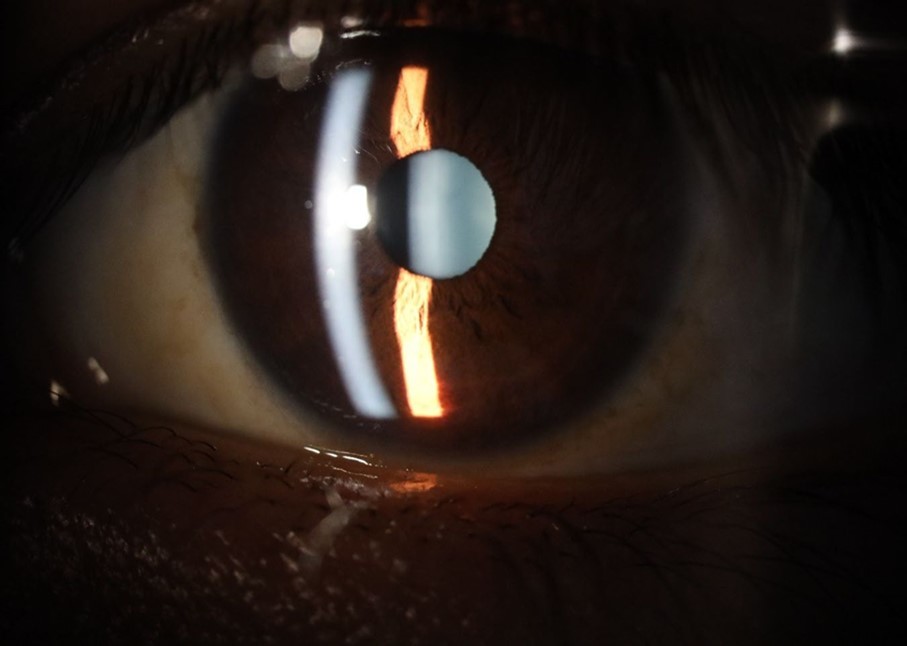

Figure 20.The mirror reflection of the affected (right) eye continues to improve.

Figure 21.The anterior segment of the right eye responds with difficulty to mydriatics, which is usual in diseased eyes.

Figure 25.Mirror reflection of the affected eye (right side), with good appearance. This indicates that the transparent media of the eyeball (Cornea, anterior chamber, lens, and vitreous) are in good condition.

Figure 26.The macrograph of the anterior segment of the right eye (affected) shows very good transparency of the cornea, anterior chamber, lens, and vitreous.

Figure 31.The photograph of the right eye shows an almost normal mirror reflection, as well as a better pupillary dilation.

Figure 32.The macro photograph of the right eye shows us a cornea, anterior camera, and crystalline lens in very good condition.